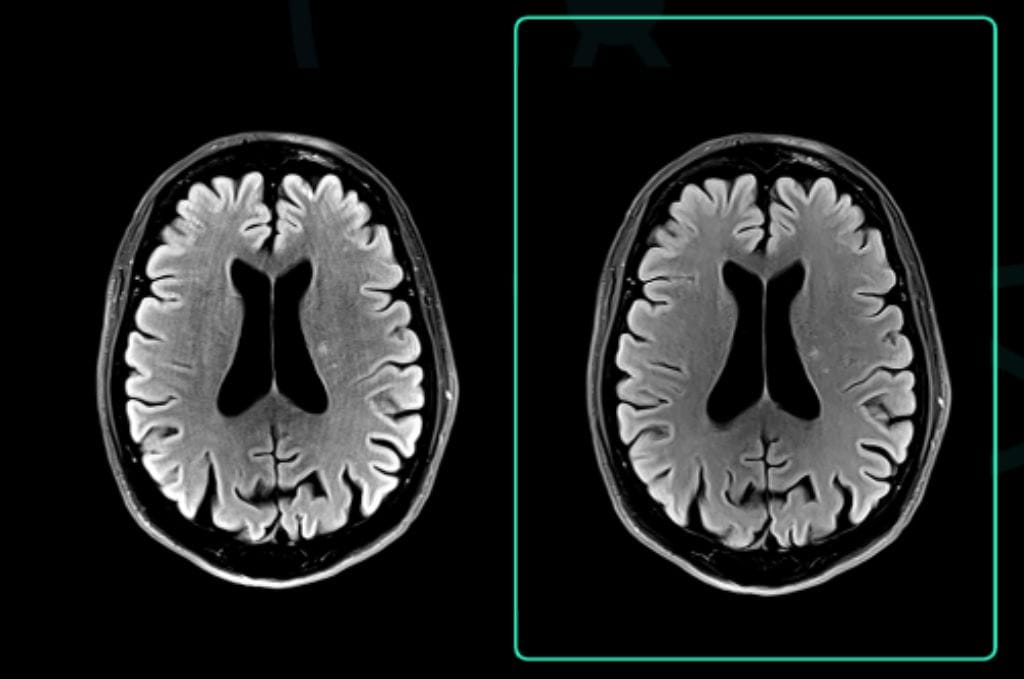

Varredura original: 3:24

Tempo Acq: 320×320

Varredura acelerada aprimorada por SubtleMR™

Tempo Acq: 1:09